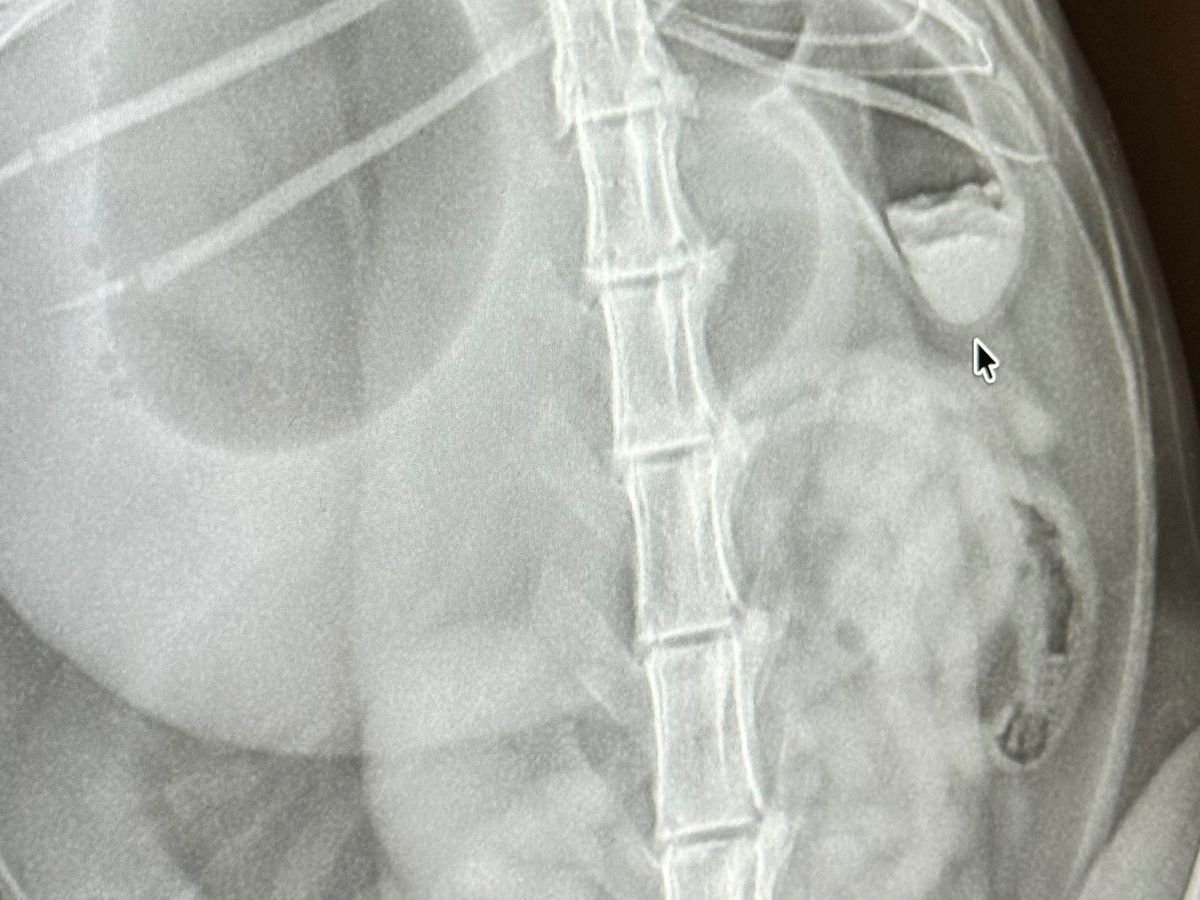

Our beloved Pinto has to get surgery due to a foreign object that is blocking his intestines and hasn’t ate since Wednesday 04/01/26. He’s been in pain and surgery is the only way. I never ask anyone for help with the kitties, but everyone who meets him can tell you that he’s the sweetest boy ever and doesn’t deserve to be in pain. Since Bryan is deployed, it’s just me taking care of the kitties and funds are low asa I am full time student. If you can donate to his surgery fund that will be amazing and very appreciated. Thank you